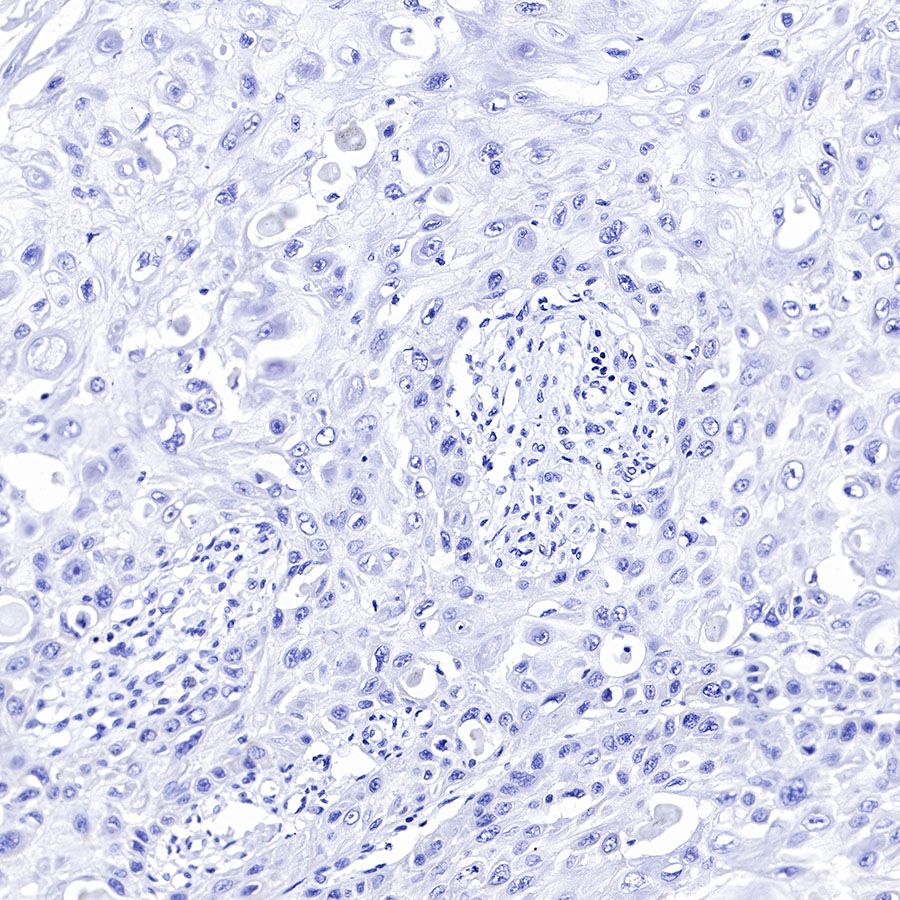

| IHC-P |

1:500-1:2000 |

Background

CK-LMW is low molecular weight cytokeratins and is expressed in monolayer or glandular epithelium of normal or tumor tissues, such as thyroid, breast, gastrointestinal or respiratory epithelium. It is expressed in adenocarcinoma and the vast majority of nonkeratinizing squamous cell carcinoma, but not in keratinizing squamous cell carcinoma. It combined with CK5/6 for diagnosis of adenocarcinoma and squamous carcinoma.